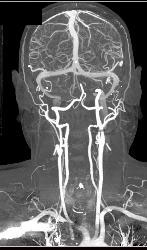

CTA With Dual Energy and Bone Removal